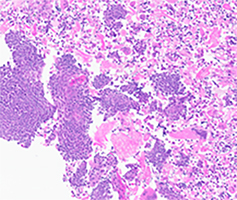

Fine needle aspiration of the mass revealed scattered aggregates of markedly atypical basaloid squamous cells with brisk mitosis in a background of necrosis morphologically meeting the cytologic diagnostic criteria for squamous cell carcinoma. The cells showed P40 positivity with focal and patchy P16 immunoreactivity. But negative for high-risk HPV and androgen receptor immunostaining (Fig. 3A-3E).

Fig 3A: FNA